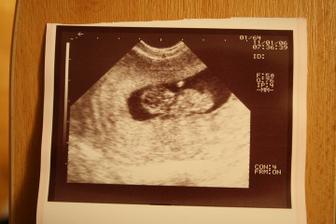

6.1.2011 třetí kontrola (11tt) - dostali jsme těhu průkajdu, byli jsme na odběru krve, vyšetření moči a dostali jsme tři ultrazvuky. Mimísek měří 33mm